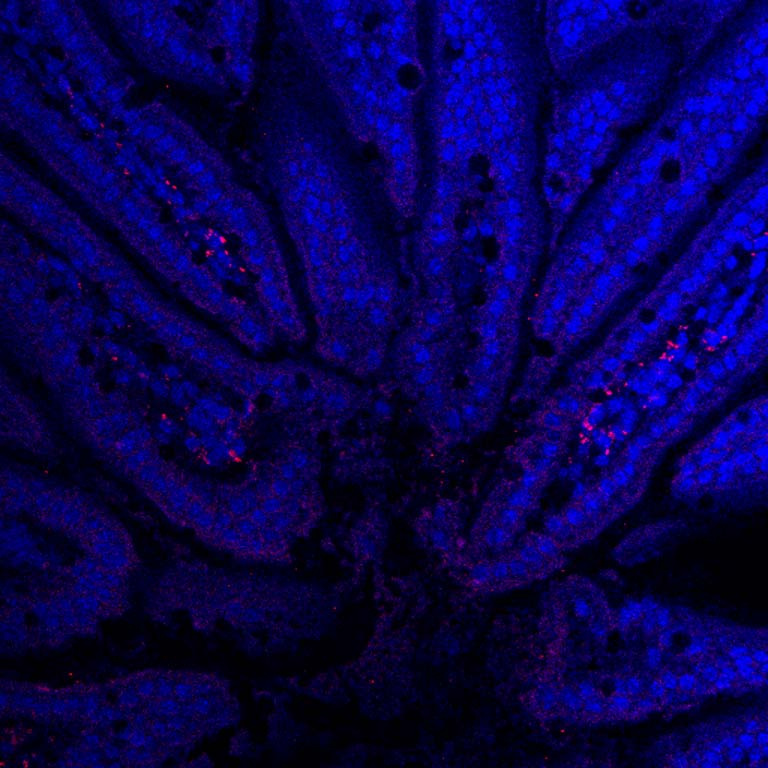

Nanoparticles (red) loaded with drugs are passing across the intestines into the bloodstream after oral ingestion. If loaded with insulin, the nanoparticles could be used in an insulin pill that could be taken by mouth for treatment of diabetes.